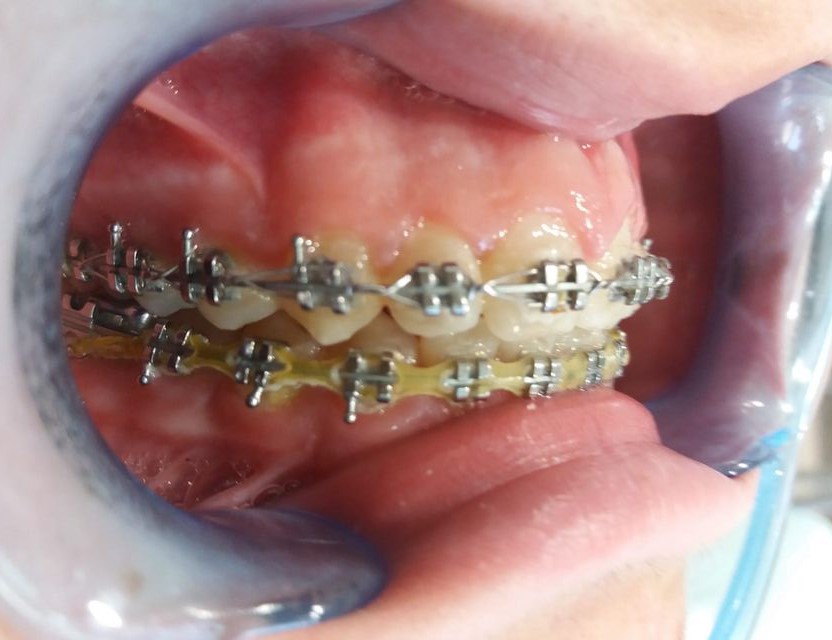

Vamos a ver el tratamiento de ortodoncia de un paciente de 11 años de edad en el que se observa una clase II de tipo dento-alveolar. Tiene un perfil de ligera protrusión del maxilar superior y retrusión de la mandíbula. Los incisivos inferiores llegan a contactar con el paladar superior pero muy hacia atrás. Esto le da un perfil de pájaro. Siendo la causa diversa en las que se mezcla diferentes parafunciones como interposición del labio inferior entre los dientes incisivos superiores e inferiores, o también interposición lingual al tragar etc. Es decir son los músculos (labio, lengua etc.) con sus malos hábitos los que producen las mal oclusiones e incluso trastornos del desarrollo óseo maxilomandibular normal. Es decir los músculos de la cara son los arquitectos de los huesos faciales, en este caso que exponemos para mal.

El tratamiento que se propone es alineamiento dental y estimular un desarrollo o crecimiento mandibular con algo que estimule dicho crecimiento. Este “algo” son los “aparatos funcionales” que actúan como si fueran poderosos músculos que tienden a empujar o estirar (según se diseñe) las estructuras dento-óseas de forma que estimula su crecimiento, siendo, que por su edad, está en época de máximo crecimiento. La mandíbula es un hueso capaz de crecer hasta los 25 años si se la estimula correctamente. Este aparato funcional es una especie de “jumper” o “saltador” o “empujador” que empuja el maxilar superior hacia atrás y empuja la mandíbula hacia delante aprovechando la fuerza de cierre de la arcada dental. Se lleva durante seis meses más o menos y el paciente no se lo puede quitar, es por esto que en realidad funciona tan rápido.

Recordamos que los músculos de la cara son los arquitectos de los huesos faciales, en este caso el aparato funcional, que es como un músculo, actúa para bien. Trascurrido este tiempo el paciente lleva elásticos de cierre para cerrar espacios dentales y resto de ajustes oclusales. Posteriormente a la retirada del aparato de ortodoncia el paciente lleva retenciones fijas y removibles durante la noche que garanticen el resultado en cuanto a recidivas.